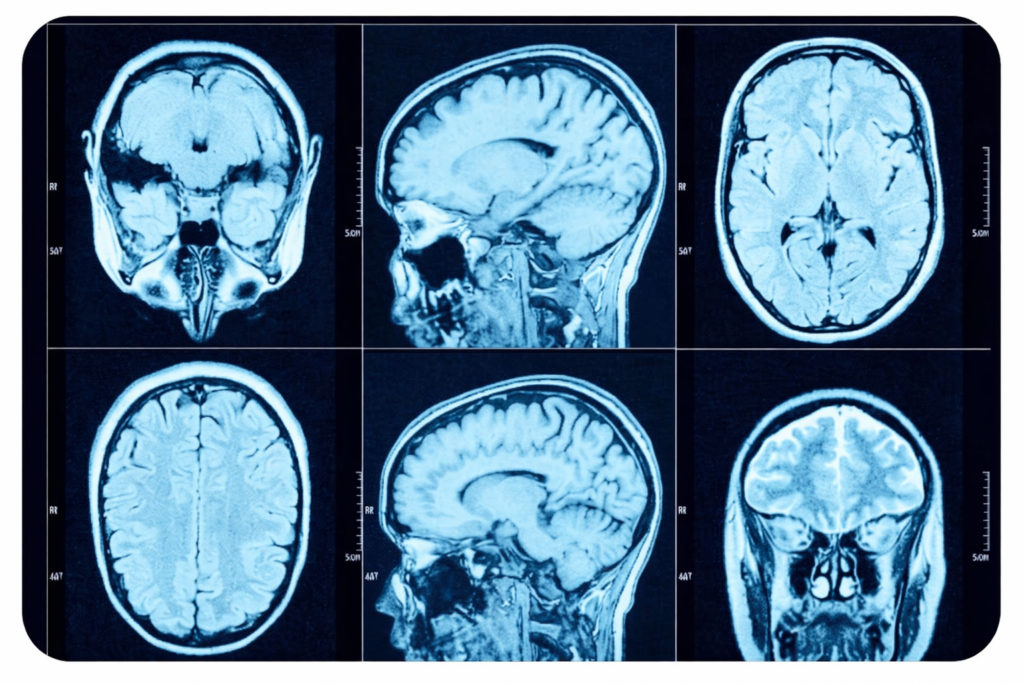

ارزش تشخیصی سی تی اسکن در ضایعات فضاگیر مغزی

ارزش تشخیصی سی تی اسکن در ضایعات فضاگیر مغزی به عنوان یکی از حیاتی ترین مباحث در نورورادیولوژی مدرن شناخته می شود که نقش تعیین کننده ای در مدیریت زمان و نجات جان بیماران مبتلا به توده های درون جمجمه ای دارد. ضایعات فضاگیر مغزی یا همان Space Occupying Lesions (SOL) شامل طیف گسترده ای […]